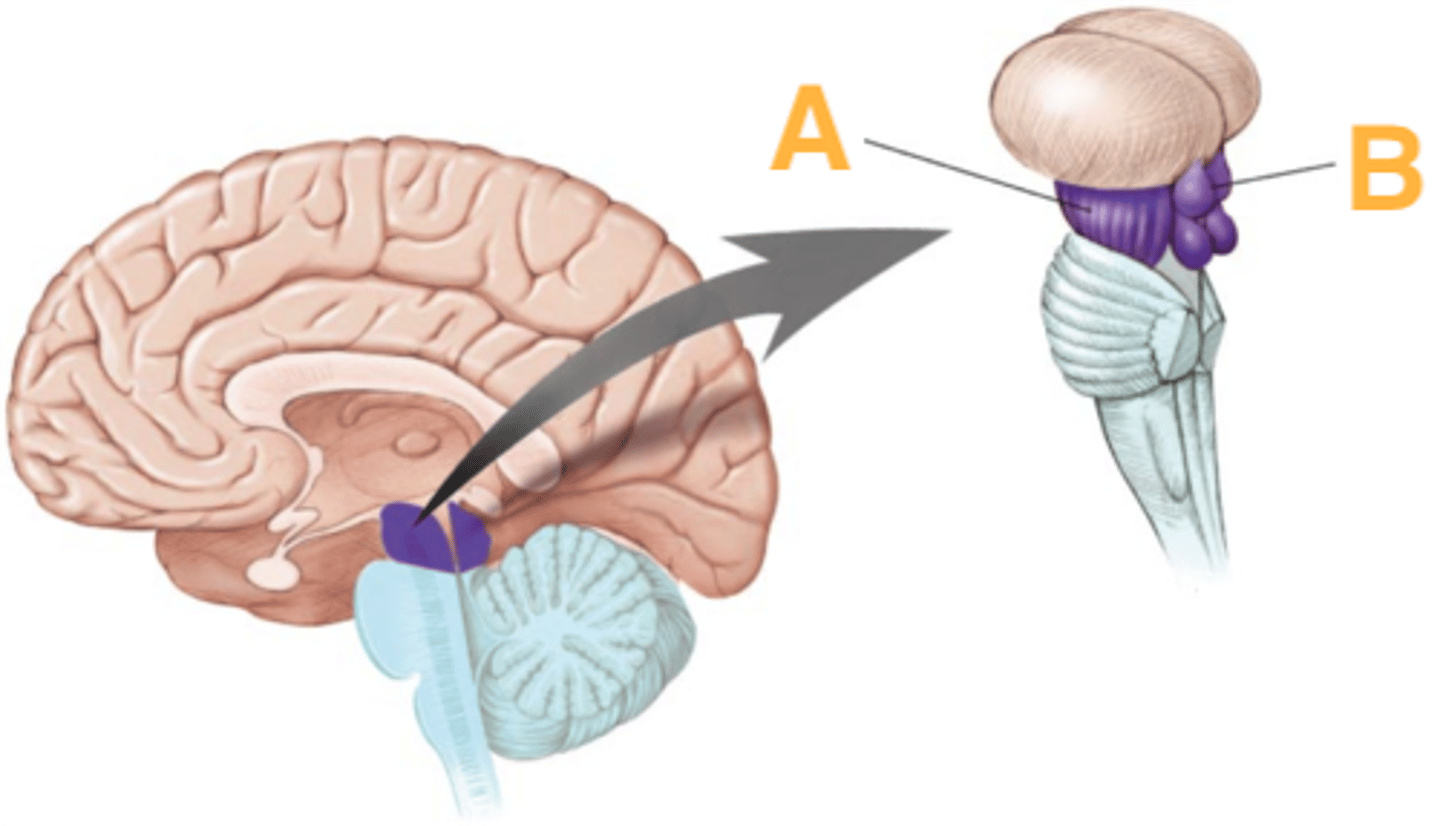

What are the 3 parts of the brain stem?

midbrain, pons, medulla

Which primary brain vesicles is the brain stem derived from?

mesencephalon, rhombencephalon

Which secondary brain vesicles is the brain stem derived from?

mesencephalon, metencephlon, myelencephalon

A

basilar portion

B

basilar sulcus

C

CN V

B

middle cerebellar peduncles

tegmentum